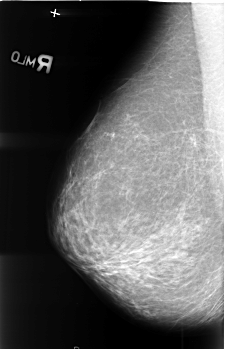

B_3410_1.RIGHT_MLO

RIGHT_CC LINES 4080 PIXELS_PER_LINE 2912 BITS_PER_PIXEL 12 RESOLUTION 50 NON_OVERLAY

RIGHT_MLO LINES 4528 PIXELS_PER_LINE 2920 BITS_PER_PIXEL 12 RESOLUTION 50 NON_OVERLAY